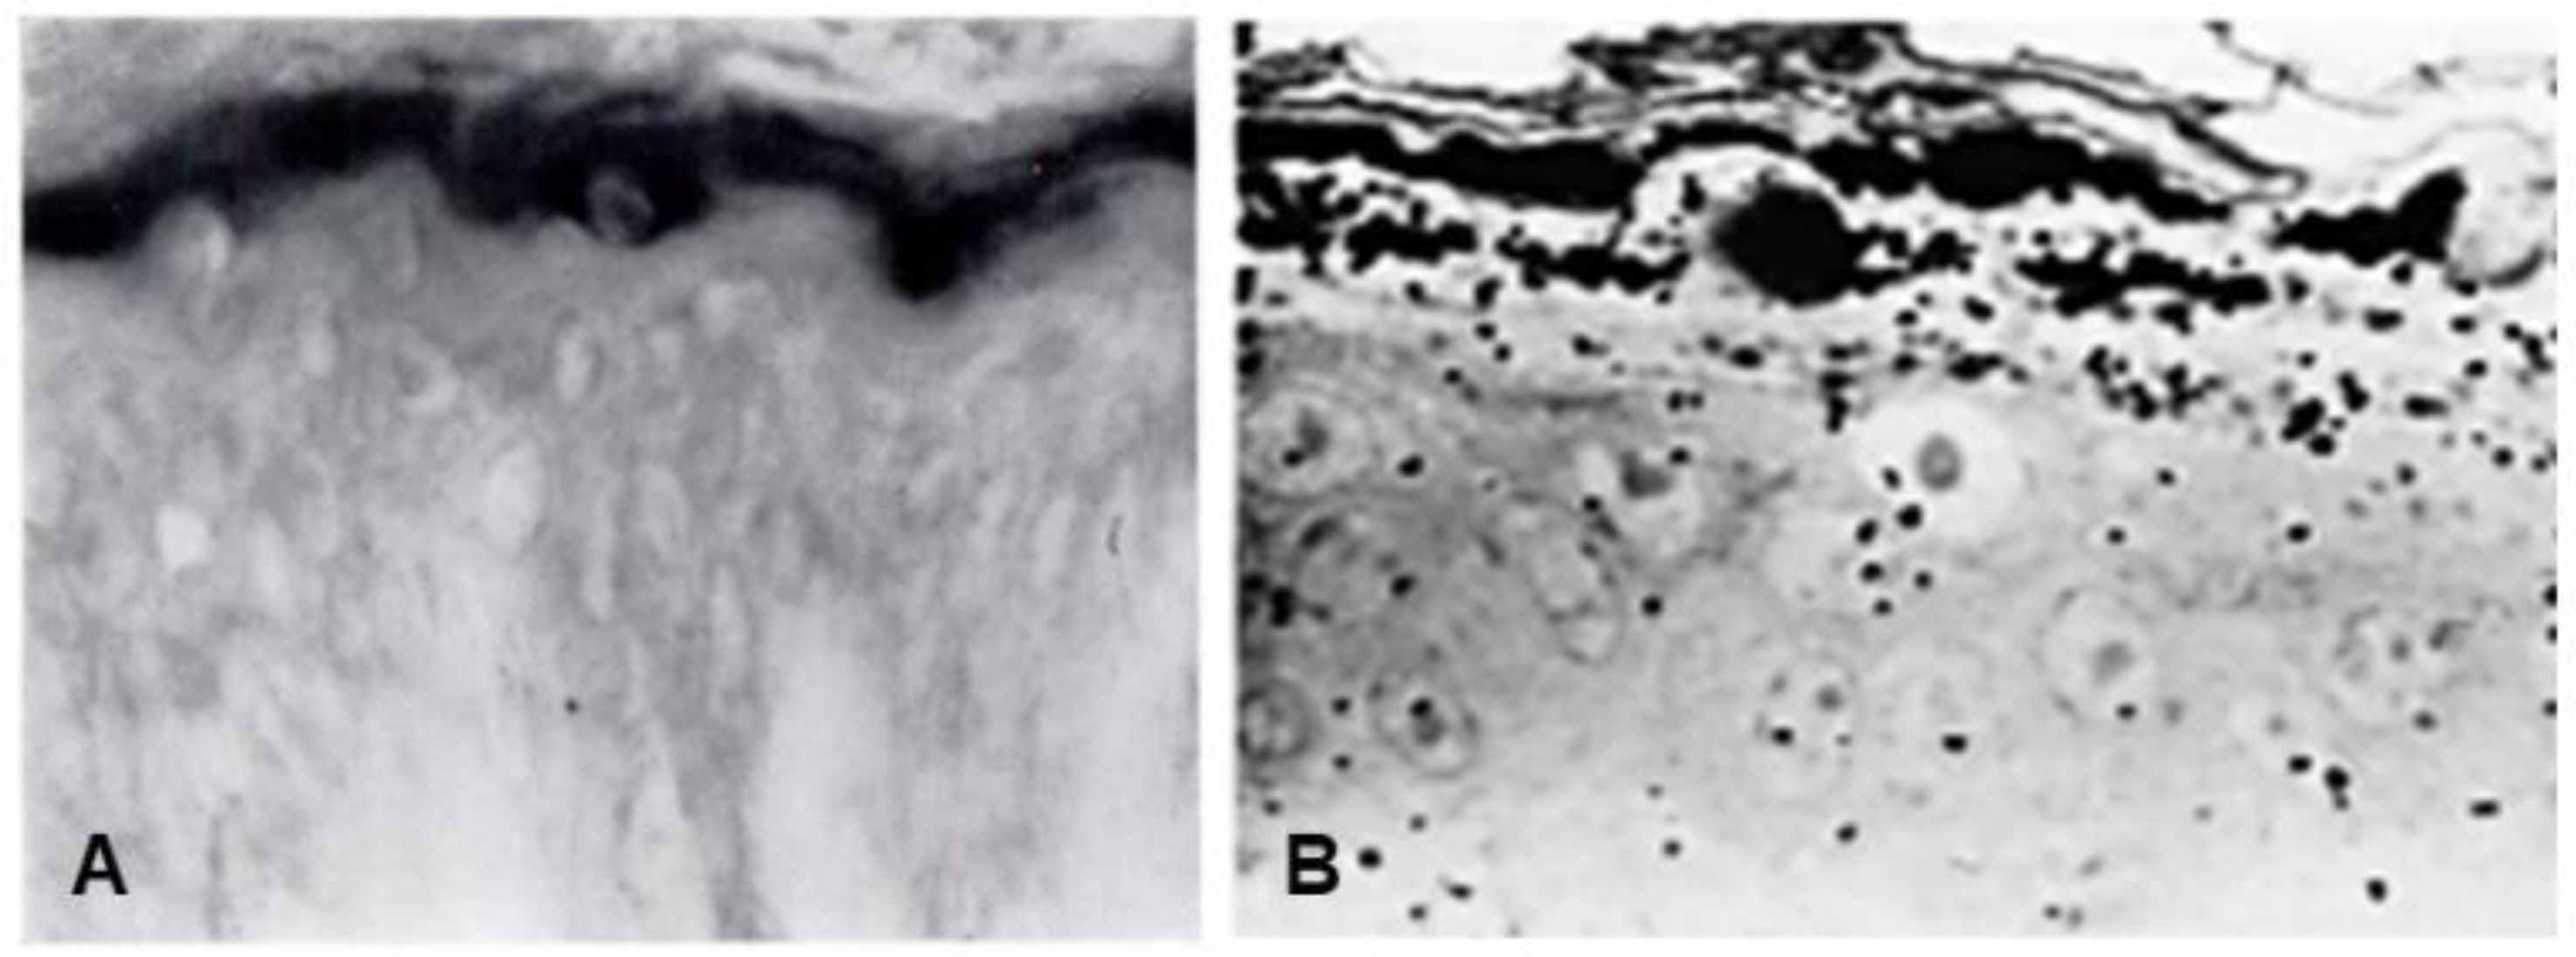

- Sibrack, L.A.; Gray, R.; Bernstein, I. Localization of the Histidine-Rich Protein in Keratohyalin: A Morphologic and Macromolecular Marker in Epidermal Differentiation. J. Investig. Dermatol. 1974, 62, 394–405. [Google Scholar] [CrossRef][Green Version]